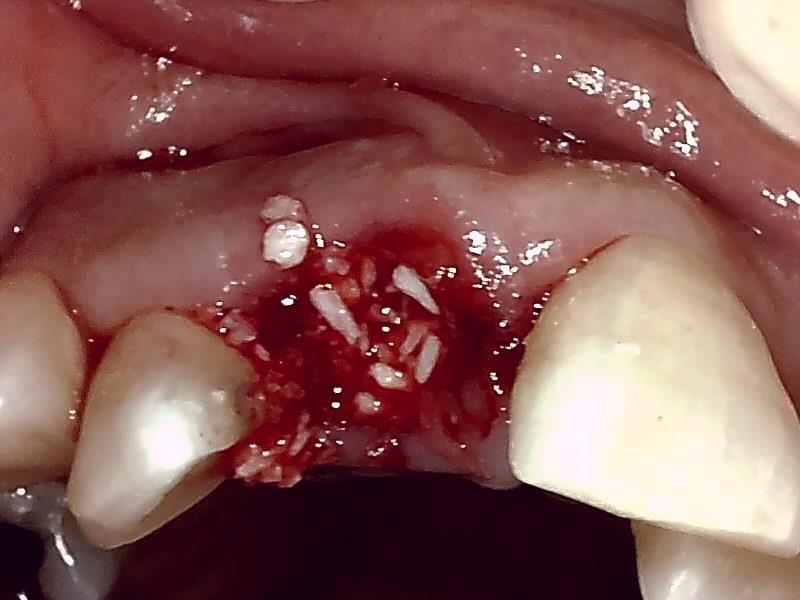

自家骨移植 GBR を施す。理想的な顎堤に築造する。

術前の時は瘦せていた顎堤が適切なグラフト手技により

しっかりした厚みのある顎堤が隆起している。